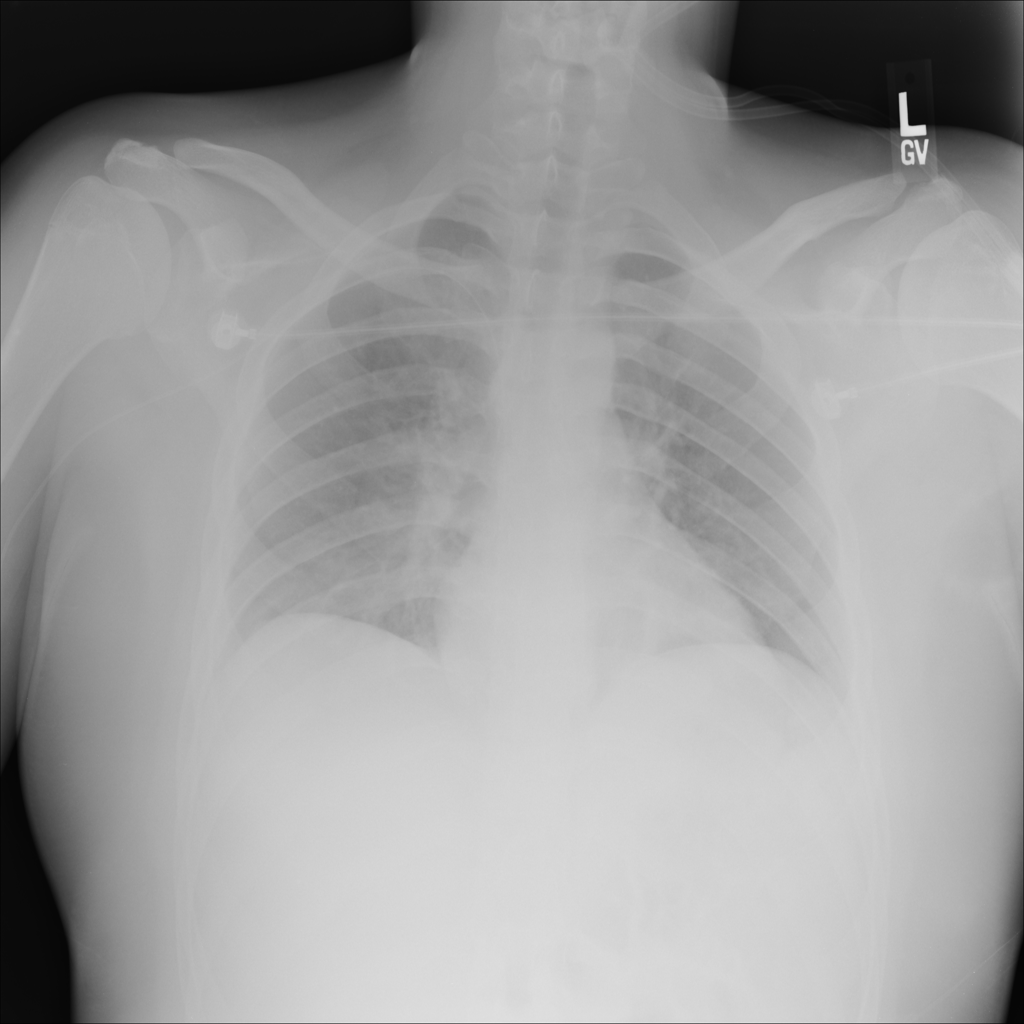

PAT-C1A7 · IMG-004Consolidation

PAT-C1A7 · IMG-004

PA